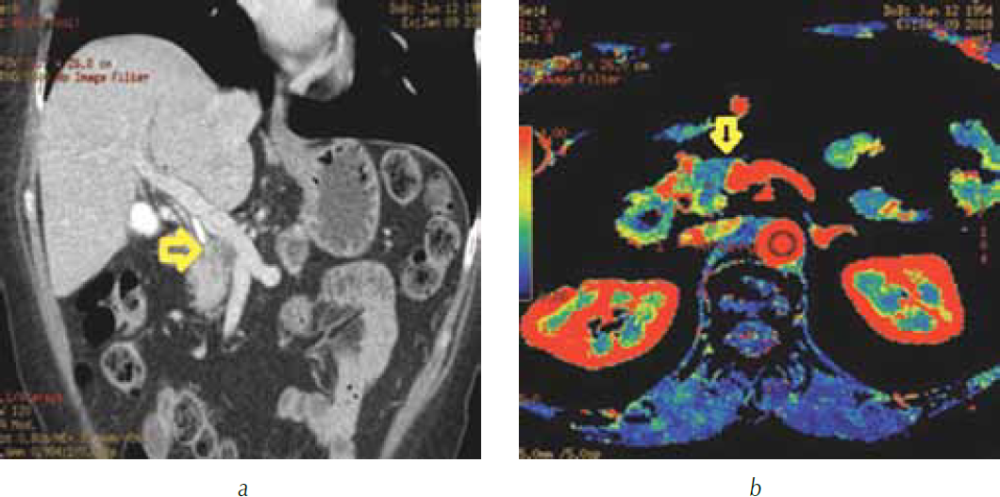

Выполнение КТ-перфузии поджелудочной железы с построением перфузионных карт позволило четко визуализировать опухоль в головке поджелудочной железы, оценить ее границы и размеры, выявить распространение на перешеек поджелудочной железы (рис. 4), измерить показатели перфузии в опухоли и неизмененной паренхиме головки (рис. 5).

Рис. 4. КТ-перфузия поджелудочной железы: а — перфузионная карта скорости кровотока (BF). Опухоль в головке поджелудочной железы определяется в виде участка синего и зеленого цветов (короткая стрелка), четко видны границы опухоли с неизмененной паренхимой, имеющей красный цвет (длинная стрелка); b — трехмерная реформация в аксиальной проекции. Панкреатическая фаза. Головка поджелудочной железы (стрелка) равномерно накапливает контрастный препарат, опухоль не видна; c — перфузионная карта скорости кровотока (BF). Размеры опухоли составили 26,6 × 20,3 мм

Рис. 5. КТ-перфузия поджелудочной железы: а — перфузионная карта скорости кровотока (BF). В опухоли (участок синего цвета) установлен ROI2, в не вовлеченной в опухолевый процесс ткани головки (участок красного цвета) ROI3; b — график зависимости «время – плотность». Красным цветом (№ 1) обозначена зависимость показателей «время – плотность» в брюшной аорте, красным цветом (№ 2) в опухоли, зеленым цветом (№ 3) в не вовлеченной в опухолевый процесс ткани поджелудочной железы. Показатели перфузии в опухоли составили: BF — 37,5 мл/100 г/мин, BV — 3,3 мл/100 г, MTT — 5,5 с; в неизмененной паренхиме головки: BF — 117 мл/100 г/мин, BV — 10,6 мл/100 г, MTT — 8 с